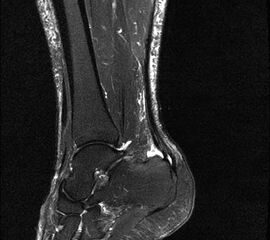

Hier befindet sich ca. 3-5 cm proximal des Tuber calcanei ein als „kritische Zone“ benannter Bezirk, der durch eine ungünstige arterielle Blutzufuhr gekennzeichnet ist (letzte Wiese). Hier finden sich häufig spindelförmige Schwellungen, die bei MRT-Diagnostik nicht selten partielle Nekrosen und Partialrupturen der Achillessehne aufweisen (Abb. 14).

Die sonographische Diagnostik eignet sich primär zur Erkennung schmerzhafter Prozesse im Verlauf der Achillessehne und kann bei Bedarf durch Röntgen bzw. MRT ergänzt werden. Besonders bei längeren Verläufen und kräftigen spindelförmigen Schwellungen (>9mm, Normwert <5mm) im Bereich der kritischen Zone sollte ein MRT zum Ausschluss von Nekrosezonen und Partialrupturen vor Therapiebeginn veranlasst werden. Die sonographisch leicht zu erfassende Veränderung der Sehnendicke im mittleren Sehnenanteil ist ein guter Indikator für die Schwere der Erkrankung und die Beurteilung des Behandlungsverlaufes. Die sichtbaren Veränderungen am distalen knöchernen Ansatz der Sehne sind diskreter.

Insbesondere bei größeren Partialrupturen (Abb. 14) sollten operative Verfahren erörtert werden. Kleinere Partialrupturen sind der ESWT gut zugänglich, wie die beiden nachfolgenden Beispiele zeigen:

In Abhängigkeit des Befundes kann die Verwendung eines Vacoped-Stiefels für die Zeit der Therapie sinnvoll sein. Eine MRT-Kontrolle nach Therapie einer Partialruptur kann nach 5-6 Monaten durchgeführt werden.